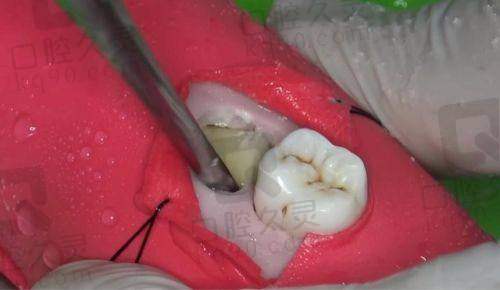

深圳友睦口腔在拔下颌正位萌出智齿时采用了精良的微创拔牙技术,这项技术有着诸多优势。

精细操作:医生借助精良的口腔检查设备,如口腔CT等,能够清晰地了解智齿的位置、形态以及与周围组织的关系,从而在拔牙过程中进行精细的操作,大大减少了对周围健康组织的损伤。

创伤小:传统拔牙可能会造成较大的创口,而微创拔牙技术通过使用特殊的器械,在尽可能小的创口下将智齿拔除。这样不仅术后疼痛减轻,而且修复时间也会缩短,让你能更快地修复正常生活。